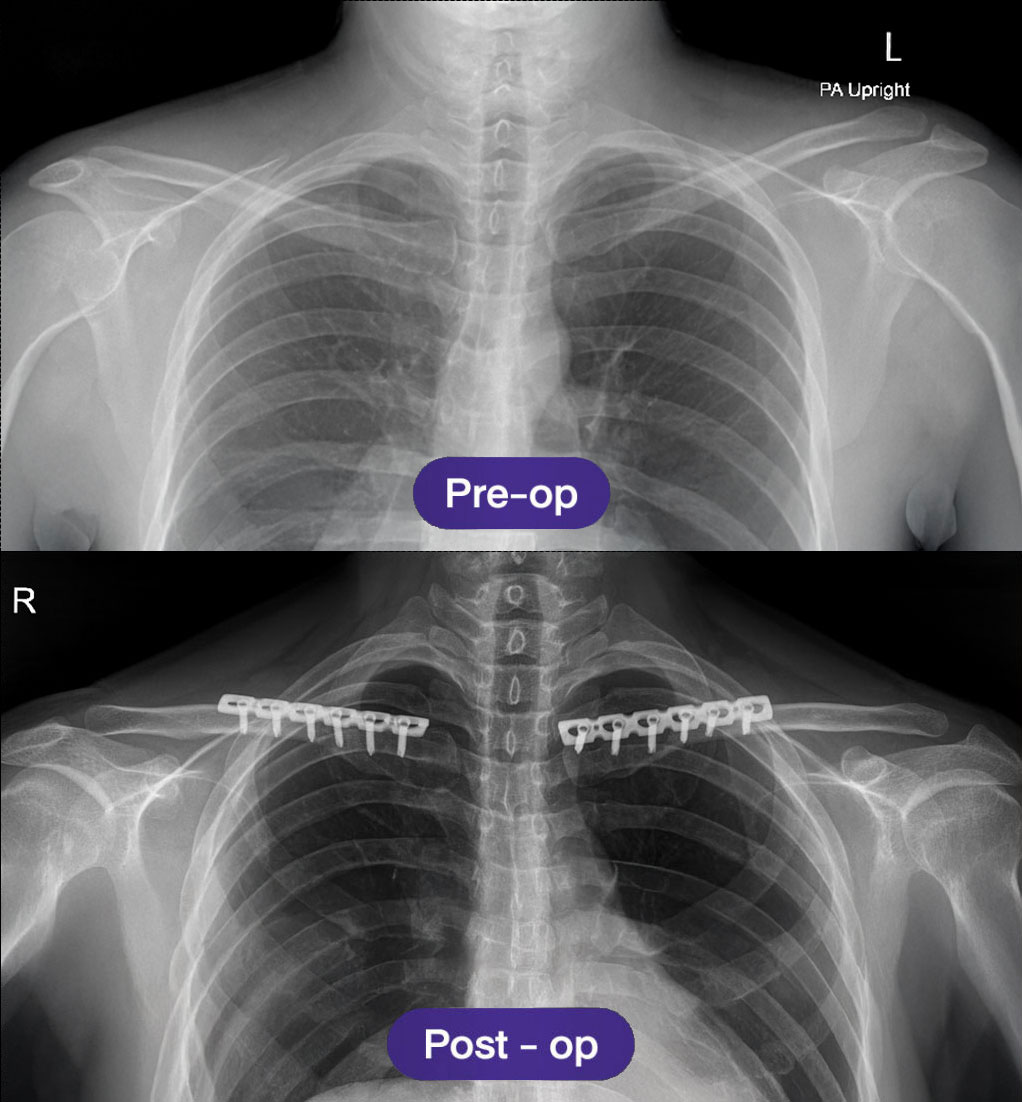

📌 การเอกซเรย์กระดูกไหปลาร้าหลังการผ่าตัด จะดำเนินการเป็นประจำในการติดตามผลครั้งแรก เพื่อยืนยันการจัดแนวของกระดูกที่เหมาะสมและความคืบหน้าของการสมานตัว

การเอกซเรย์หลังการผ่าตัดและคำแนะนำหลังการผ่าตัดลดความกว้างหัวไหล่

- การเอกซเรย์กระดูกไหปลาร้าหลังการผ่าตัด จะดำเนินการเป็นประจำในการติดตามผลครั้งแรก เพื่อยืนยันการจัดแนวของกระดูกที่เหมาะสมและความคืบหน้าของการสมานตัว